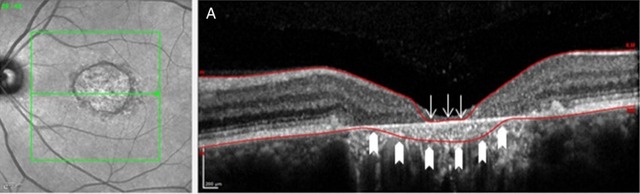

研究表明,SD-OCT 可以监测 STGD1 的视网膜体积下降情况,但是需要手动矫正视网膜界限识别错误等程序错误,如图 1。作者认为,视网膜厚度和体积的测量包括视网膜色素上皮层可能更有利于监测 STGD1 的萎缩进程。

图 1 左侧为共焦激光扫描检眼镜图像,右侧为相应横截面的单个 B 扫描。图 A 箭头所指部分为软件对视网膜内外界限的识别错误;图 B 为手动矫正错误后。